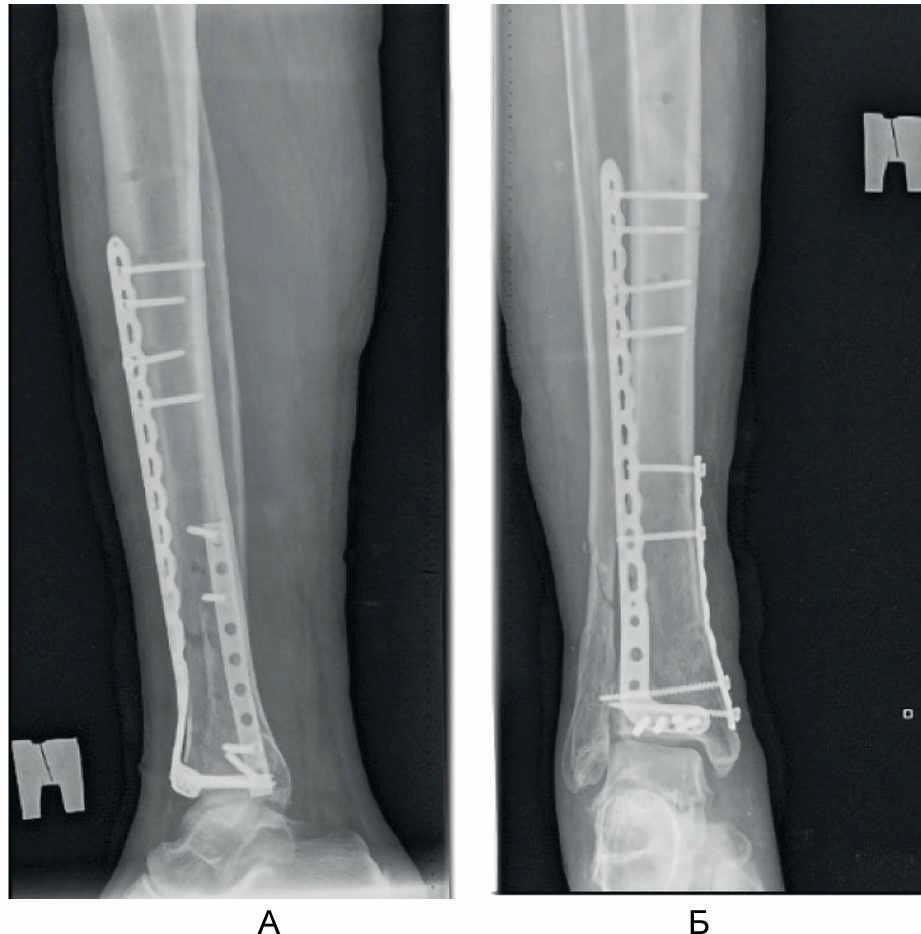

Выполнили поперечный разрез кожи и поверхностной фасции на передней поверхности голени на 1–2 см выше проекции щели голеностопного сустава. Путем продольной тупой диссекции сформировали 2 окна для доступа к большеберцовой кости между проксимальной и дистальной порциями удерживателя сухожилий разгибателей: 1-е – между длинным разгибателем I пальца стопы и длинным разгибателем пальцев стопы, 2-е – латеральнее длинного разгибателя пальцев стопы. Через сформированные окна снизу вверх эпипериостально ввели анатомически предызогнутую пластину для дистального отдела большеберцовой кости до тех пор, пока дистальный ее конец не достиг уровня субхондрального слоя большеберцовой кости. Затем пластина была предварительно фиксирована к кости спицей Киршнера. Окончательную репозицию перелома в метафизарной зоне выполнили чрескожно с использованием остроконечных репозиционных щипцов. На уровне проксимального конца пластины на переднелатеральной поверхности голени осуществили проксимальный разрез кожи и мягких тканей длиной 3 см, минимально необходимый для визуализации пластины. Пластину фиксировали к кости винтами с угловой стабильностью, введя через дистальный и проксимальный доступы ниже и выше зоны перелома, соответственно, по 4 винта. Обнажение зоны метафиза и области перелома не выполняли, что сохранило перифрактурную гематому и создало оптимальные условия для сращения перелома (рис. 4).

Рис. 4. Малоинвазивный остеосинтез минимизирует ятрогенную травму мягких тканей и нарушение кровоснабжения отломков кости. А – закрытая репозиция остроконечными репозиционными щипцами; Б, В – интраоперационные рентгенограммы при установке опорной пластины.

Затем выполнили медиальный дистальный разрез кожи и мягких тканей длиной 2 см, начиная его на 2 см проксимальнее верхушки медиальной лодыжки и продолжая его в проксимальном направлении. Далее предварительно отмоделированную по форме дистального отдела большеберцовой кости линейную пластину 1/3 трубки длиной, достаточной для перекрытия зоны перелома, провели эпипериостально снизу вверх до тех пор, пока дистальный ее конец не достиг нижнего края сделанного разреза. Затем на уровне проксимального конца введенной пластины, который хорошо пальпировался под мягкими тканями на медиальной поверхности нижней 1/3 голени, выполнили вертикальный разрез кожи длиной 2 см. Разводя кожу и подлежащие мягкие ткани, проксимальный конец введенной пластины был визуализирован в ране. Затем произвели фиксацию медиальной пластины винтами диаметром 3,5 мм, введя по 2 винта дистальнее и проксимальнее зоны перелома через медиальный дистальный и медиальный проксимальный доступы соответственно (рис. 5).

Рис. 5. Малоинвазивная имплантация металлоконструкций. А – интраоперационная рентгенограмма во время установки медиальной пластины; Б, В – интраоперационный вид конечности после установки имплантатов.

Положение отломков и имплантатов в ходе операции контролировали интраоперационной рентгеноскопией при помощи рентгеновского электронно-оптического преобразователя. Рентгенологический результат операции представлен на рис. 6.

Рис. 6. Рентгенограммы в боковой (А) и прямой (Б) проекциях после выполнения малоинвазивного накостного остеосинтеза нижней 1/3 большеберцовой кости.